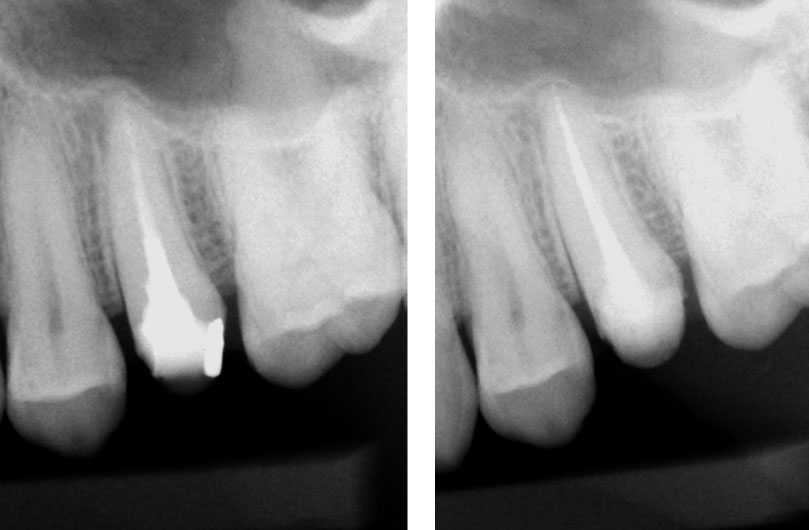

Pre-op

Residual caries seen after temp removal.

After caries removal

Cotton pellets placed over the palatal and Disto-buccal orifices to prevent the instrument from slipping into those canals.

Fractured instrument in mesio-buccal canal

Fractured instrument removed with ultrasonics

Canals cleaned, shaped and obturated

Fiberglass-post and composite core placed

Post-op

Pre-op & Post-op